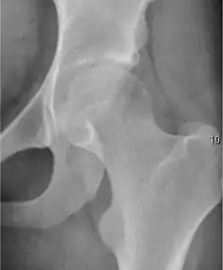

Plain radiography allows us to categorize the hip as normal or dysplastic or with impingement signs (pincer, cam, or a combination of both). Besides these, pathologic processes like osteoarthritis, inflammatory diseases, infection, or tumors can also be identified (Figure 1).[1]

- Osteoarthritis

In adults, one of the main indications for radiographs is the detection of osteoarthritic changes (Figure 1(e)). Nevertheless, radiographs usually detect advanced osteoarthritis that can be graded according to the Tönnis classifications. The grading system ranges from 0 to 3, where 0 shows no sign of osteoarthritis. Intermediate grade 1 shows mild sclerosis of the head and acetabulum, slight joint space narrowing, and marginal osteophyte lipping. Grade 2 presents with small cysts in the femoral head or acetabulum, moderate joint space narrowing, and moderate loss of sphericity of the femoral head. Grade 3 is the severest form of osteoarthritis, which manifests as severe narrowing of the joint space, large subchondral cyst with productive bone changes that may lead to deformity of the bone components of the joint, while secondary osteoarthritis due to calcium pyrophosphate deposition can be diagnosed when calcification of hyaline cartilage and fibrocartilage is detected.[1]